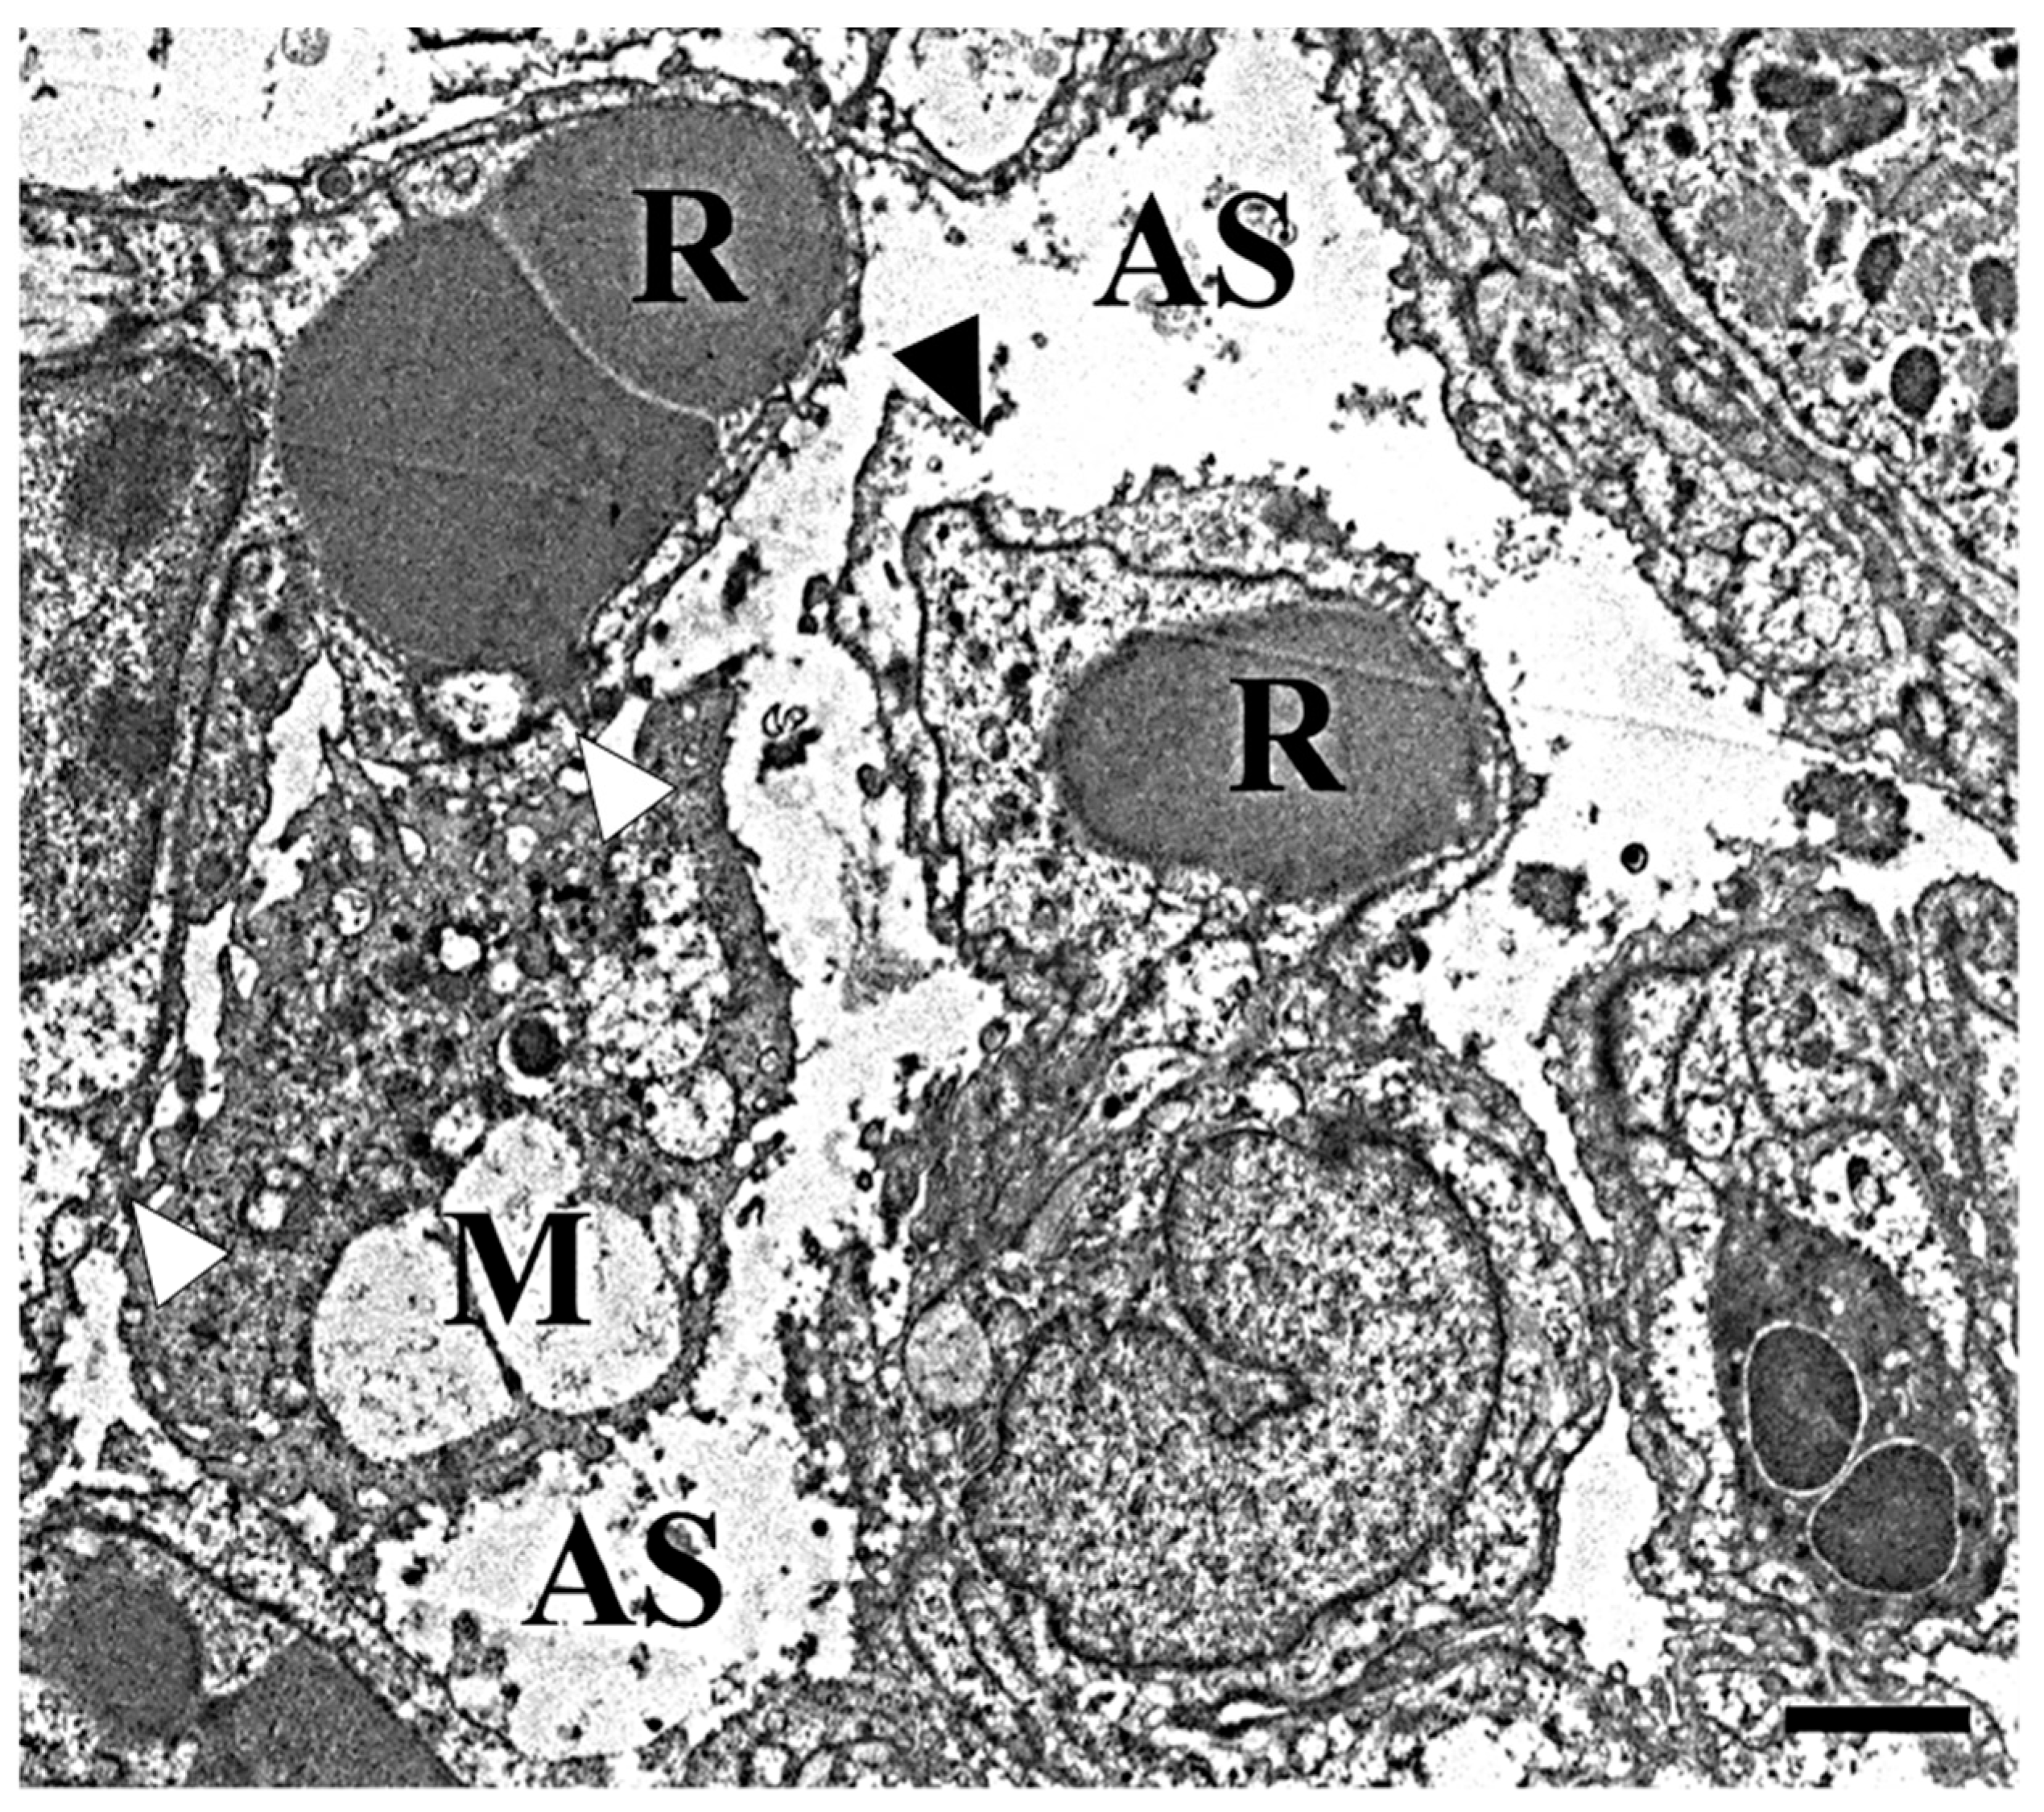

2.5. Electron Microscopy Analysis